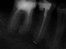

An Zahn 17 hatte sich, vom Patienten unbemerkt, eine Fistel manifestiert. Anlass für eine Übersichtsaufnahme, welche neben 2 gefüllten auch einen ungefüllten Wurzelkanal offenbarte (Bild 1). Der Verursacher der fistelerhaltenden Eiterproduktion war damit identifiziert. Um diesen Prozess zu unterbrechen, wurde in gleicher Sitzung ein Zugang angelegt, der Kanal vermessen, gereinigt, mit Einlage versehen und wieder verschlossen.

Die Behandlung fühlte sich gut an, so war die Fistel geschlossen nach 3 Wochen, als die Wurzel gefüllt wurde. Und dieses gelang trotz Haken-Wurzel fast perfekt (Bild2). Der Patient kam 8 Monate später wieder auf uns zu und bat, um Überbrückung der Lücke davor. Gross geriet das Staunen dann, die Fistel griente uns schon von Weitem an.

Zu tiefst beleidigt gab's hinten-aussen 2 neue Einlagen vor Wiederbefüllung. Und später, um die Brückenkonstruktion nicht zu gefährden, wurden im Anschluss an die Abformung kassenfreundlich, bei bestehender Anästhesie, beide äusseren Wurzeln ihrer Spitzen beraubt. (Bild 3).

Behandlungsspanne ca. 10 Monate